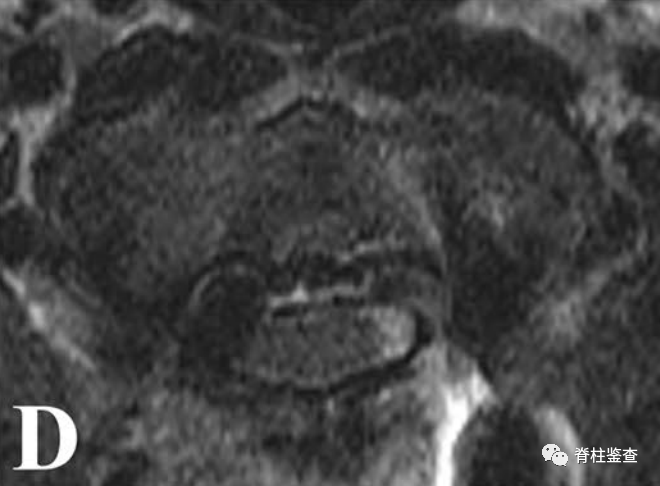

D:尽管螺钉进入椎管,但未导致神经功能损伤案例二女性,29岁